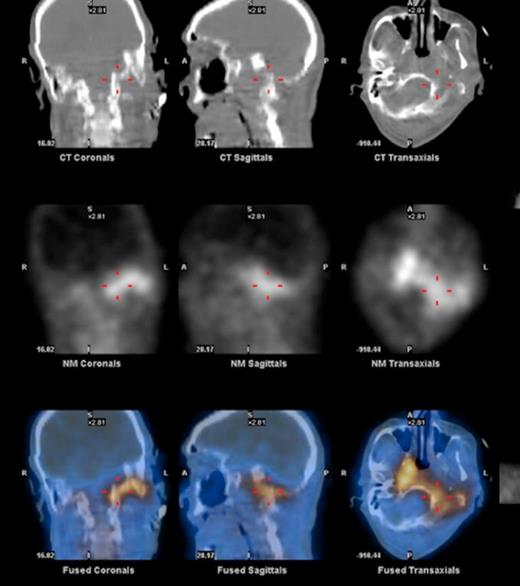

At the tertiary hospital the patient was found to be clinically wasted and weak. He also had rightward uvular deviation, absent gag reflex, weakness of the left sternocleidomastoid and trapezius, House Brackman grade 2 left facial nerve weakness and an immobile left vocal cord. This was the first time a cranial nerve examination was recorded. MRI and SPECT/CT with Gallium tracer was performed, the images acquired from which illustrate the severe extent of disease (figures 1 to 5).

He was diagnosed with MOE with extensive skull base osteomyelitis producing multiple lower cranial neuropathies. Biopsy performed by ORL/ENT surgeons grew Scedosporium apiospermum and given the extent of the infection a palliative approach was agreed upon with the patient and family.